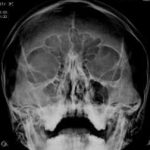

Rayos-X

Los rayos X, o radiografía, utilizan una dosis muy pequeña de radiación ionizante para producir imágenes de las estructuras internas del cuerpo. Los rayos X son la forma más antigua y más frecuentemente utilizada de las imágenes médicas. Se utilizan generalmente para ayudar a diagnosticar huesos fracturados, para buscar una lesión o infección, y para localizar objetos foráneos en el tejido blando

Estudios Convencionales